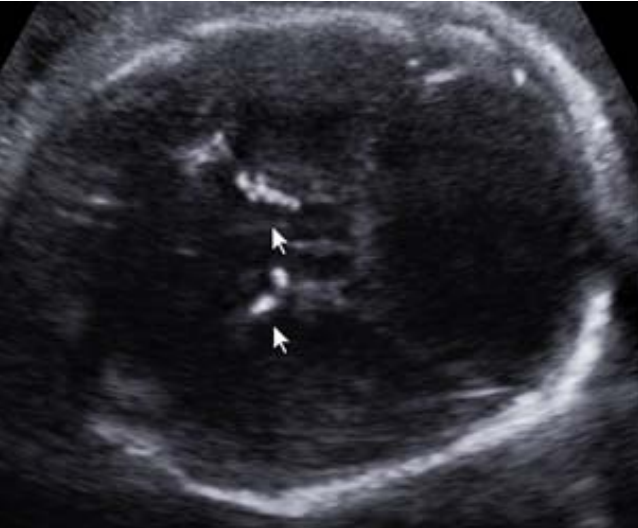

Paciente na 28ª semana, multípara, seis partos vaginais e sem pré-natal adequado vem à emergência obstétrica preocupada para mostrar uma ultrassonografia, a qual descreve uma circunferência cefálica abaixo de três desviospadrões para a idade gestacional e imagem abaixo:

Foi encaminhada para um serviço especializado, onde foi submetida à investigação diagnóstica. Na 39ª semana de gravidez, evoluiu com o parto vaginal. Ao nascimento, as alterações ultrassonográficas foram confirmadas, acrescidas de coriorretinite e atraso no desenvolvimento neurológio.

Baseado nesses sinais e sintomas, assinale a alternativa que sugere a principal hipótese etiológica fetal.